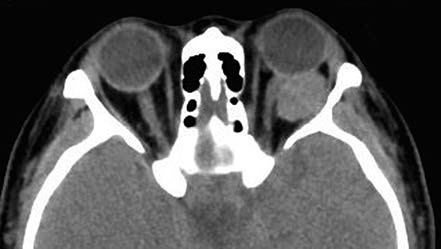

Figure 1 CT imaging of a left orbital cavernous venous malformation

The lesion is well-defined, homogeneous in density, and compresses the optic nerve.

On CT imaging, cavernous venous malformations typically appear well-demarcated and homogeneous in density. Signs such as optic nerve compression, displacement, and orbital cavity enlargement can be observed. CT imaging can also assess the degree of lesion adhesion. When fat is present at the posterior margin of the lesion, a triangular area of hypodense orbital fat is visible at the orbital apex on CT, suggesting minimal adhesion to surrounding tissues. Cavernous venous malformations without this hypodense orbital fat feature often exhibit significant adhesion. MRI findings show iso-intensity on T1-weighted images and hyperintensity on T2-weighted images. The hallmark of dynamic contrast-enhanced imaging is progressive enhancement, where small areas display early patchy enhancement that gradually becomes diffusely and homogeneously enhanced over time.